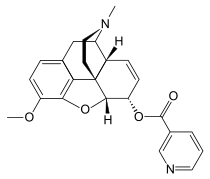

- Esters of morphine opiates: slightly chemically altered but more natural than the semi-synthetics, as most are morphine prodrugs, diacetylmorphine (morphine diacetate; heroin), nicomorphine (morphine dinicotinate), dipropanoylmorphine (morphine dipropionate), desomorphine, acetylpropionylmorphine, dibenzoylmorphine, diacetyldihydromorphine;[261][262]